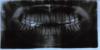

deemone Опубликовано 3 августа, 2010 Поделиться Опубликовано 3 августа, 2010 В августе 2009 болели 3-4 нижних крайних левых зуба 4 дня. Сходил к стоматологу, она с помощью пульптестера определила, что воспалился 3-й крайний нижний зуб (6-ка), удалила нерв. Через 2 дня поставила большую пломбу. После этого ходил месяц и ничего не беспокоило. В октябре 2009 г. начали снова болеть ноющей болью левые нижние зубы. Но определить сложно, где болит. Предположительно эпицентром является тот зуб, у которого удалили нерв, но и рядом зубы поднывают, причём в разное время ноют разные зубы. Часто появляется боль в верхних левых зубах (также сложно определить где именно болит). В общем картина такая: 70% от всей времени боли - болит в районе нижней левой 6-ки, 15% - в районе верхней левой 6-ки, 15% - левая нижняя 3-ка и 4-ка. И так уже больше, чем полгода (за это время характер боли не изменился). Боль несильная, ноющая, терпимая, длится продолжительностью 20-80 минут, в общей сложности 2-4 часа каждый день. Когда что-то делаю, то не сильно обращаю на боль внимания, а если просто сижу и смотрю ТВ, то она очень надоедает. Ни разу за это время не проснулся ночью из-за зубов (когда был воспалён нерв пару лет назад - спать было невозможно). В ноябре 2009 ходил лечить кариес на одном из зубов на правой стороне, заодно и поинтересовался об этой проблеме (правда тогда поднывали плюс к этим ещё и некоторые зубы на правой стороне). Врач постучала по всем зубам, ничего не болело, и сказала, что, наверное, не в зубах дело, и стоит обратиться к невропатологу. Я подумал, что возможно это из-за смены работы и других стрессов и должно само пройти. К невропатологу не ходил… В июне 2010 снова обратился к другому стоматологу по этой проблеме - посмотрела, постучала по зубам, сделала снимок, и также сказала показаться невропатологу. В июле 2010 левый низ начал больно реагировать на холодное (на горячее больной реакции не было), купил Colgate Pro-Relief - реакция на холодное исчезла. В июле 2010 добрался я до невропатолога, он даже не дослушал мой рассказ, а сразу поставил диагноз - невропатия 1-й ветви тройничного нерва. Выписал лекарства на 10 дней (диклоберл, найз, карбамазепин), сказал, что всё пройдёт. В итоге ни капли изменений я не заметил, болит так же.Полных мне 23 года. Простудными заболеваниями болею не чаще 1-2 раза в год.Помогите, пожалуйста, надоело терпеть эту постоянную боль, да и боюсь, что это может во что-нибудь плохое превратиться, если запустить. Хотя бы определить, к какому врачу обращаться (стоматологу или невропатологу). Лично мне кажется, что скорее всего в одном из нижних зубов воспалён нерв. Можно ли как-то определить, что в конкретном зубе воспалён нерв?Заранее огромное спасибо! Ниже прикреплены снимки зубов:1. панорамный снимок (июнь 2010) - http://422405.ucoz.ru/1.jpg2. панорамный снимок (декабрь 2008) - http://422405.ucoz.ru/2.jpg3. снимки левой нижней 6-ки перед удалением нерва и после пломбировки каналов - http://422405.ucoz.ru/3.jpg Ссылка на комментарий

Maximvs Опубликовано 6 августа, 2010 Поделиться Опубликовано 6 августа, 2010 (изменено) В августе 2009 болели 3-4 нижних крайних левых зуба 4 дня.......снимки очень плохого качества. Но может быть причиной нижняя восьмерка - она очень близко к нижнечелюстному нерву расположена. Давление на нерв (особенно если есть какой-то процесс в этом зубе ) может "отдавать" в 6 и в 7 (они далее по ходу нерва). Рекомендации:1. Сделать компьютерную томограмму.2. Дальнейшие поиски причины - после КТ. (как один из дальнейших вариантов - удаление 8 зуба может снять симптомы) Изменено 6 августа, 2010 пользователем Maximvs Ссылка на комментарий

айка Опубликовано 6 августа, 2010 Поделиться Опубликовано 6 августа, 2010 Я ничего не увидела в этих снимках, но покопалась бы предметно в восьмерках. Ссылка на комментарий

igorstom Опубликовано 7 августа, 2010 Поделиться Опубликовано 7 августа, 2010 В первую очередь обратите внимание доктора на нижний восьмой слева, а именно с дистальной (задней) стороны на предмет скрытой кариозной полости. По снимку сложно судить. Но вроде как на последней ОПГ с дистальной стороны 8-го что-то прослеживается. Также, в зоне бифуркации (раздвоения корней, то есть между корнями) шестого нижнего слева имеется затемнение. Что говорит о разрежении костной ткани и возможном хроническом воспалении в данном участке.И хотелось бы спросить про состояние зубо-десневых карманов, и именно между зубами. Есть ли болезненность при зондировании или надавливании на эти участки, в области подозреваемых нижних слева 6, 7 и 8-го зубов (и верхних тоже)? Пропальпировать (надавливать) Вы и самостоятельно сможете. Ссылка на комментарий